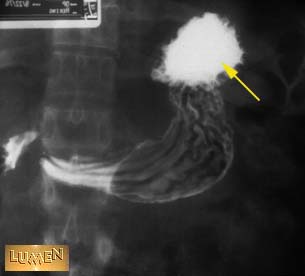

Question: Identify.

Fundus of stomach.